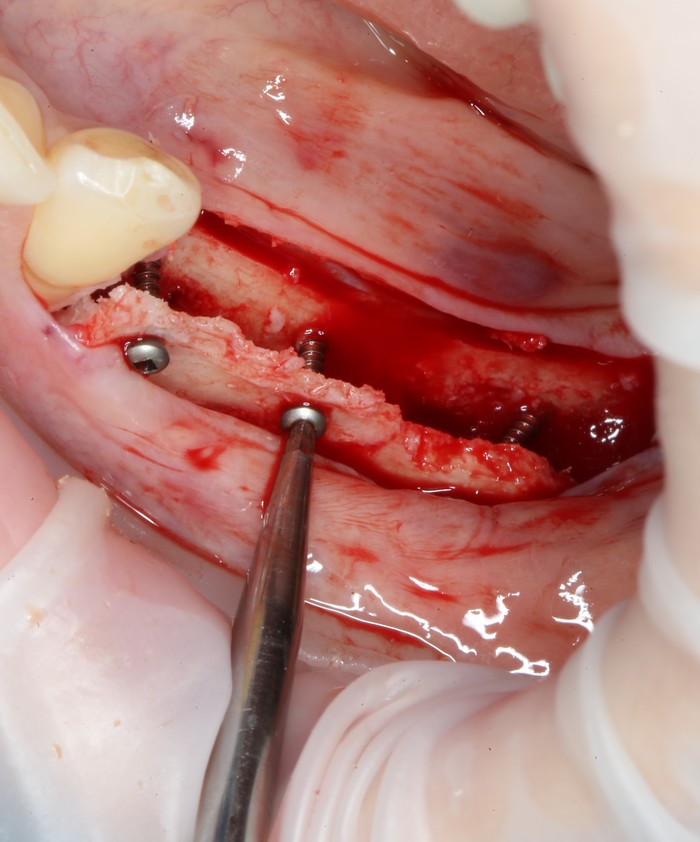

Уже на следующий день была запланирована имплантация.

Дабы не перегружать вас обилием одинаковых картинок, я оставлю один рентгеновский снимок, но отмечу, что установка имплантатов на верхней и нижней челюсти проводилась с разницей в 10 дней.

На верхней челюсти было дополнительно удалено два боковых резца с одномоментной установкой имплантатов, так же они были установлены в области четверок и шестых зубов. Дополнительно было проведено наращивание костной ткани - двусторонний синус - лифтинг. О том, что это такое, можно почитать ТУТ и ТУТ.